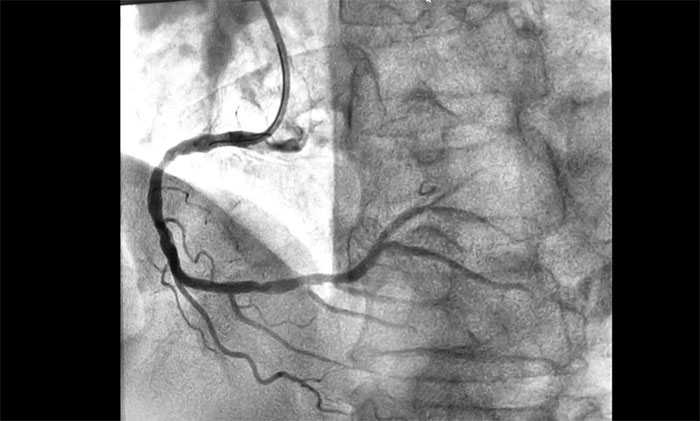

近日,上海藍(lán)十字腦科醫(yī)院為一名急性心;颊邔(shí)施介入手術(shù)。該患者因“間斷心前區(qū)不適伴咽部束縛感7小時(shí),全身乏力3小時(shí)”入院,綜合其病史和相關(guān)檢查確診其為急性下壁心肌梗死,隨時(shí)有猝死風(fēng)險(xiǎn),手術(shù)指征明確。經(jīng)球囊擴(kuò)張和支架置入,開通閉塞血管,助其恢復(fù)心肌供血。

▲ 術(shù)后,血管順利開通